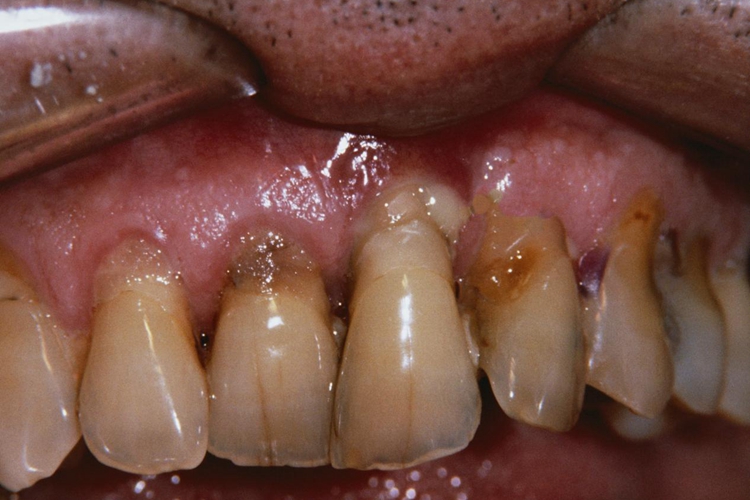

其他症状:血卟啉病还可能出现腹痛、恶心、呕吐、腹胀、咖啡色尿以及牙齿呈棕红色等症状。